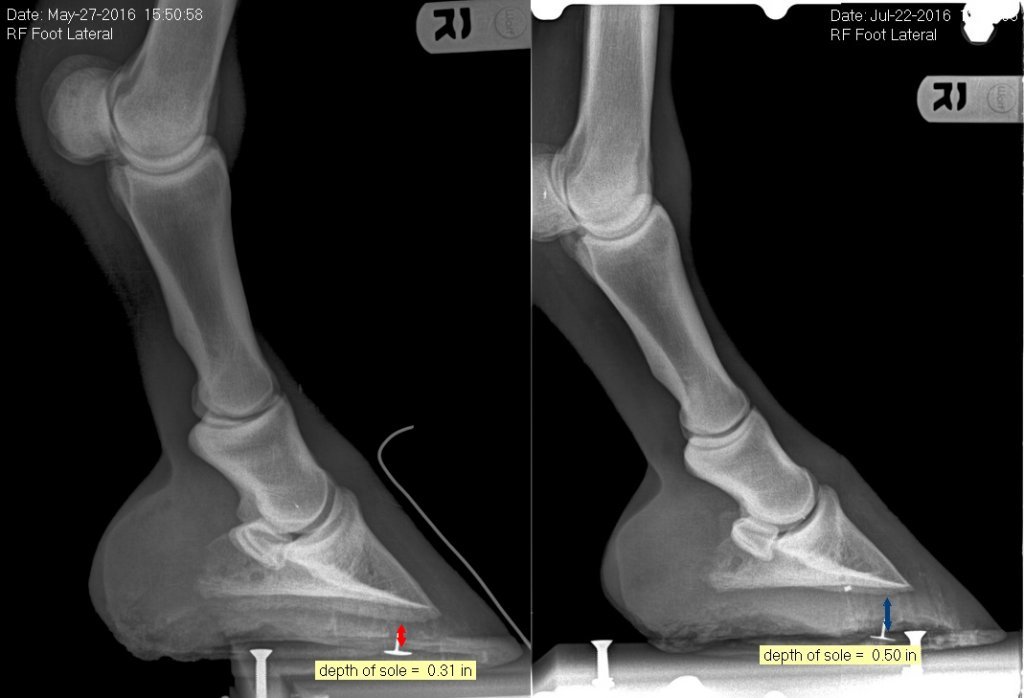

Before and after x-rays of a horse treated with pour-in pads.

To regain and maintain sole thickness, pour-in pads can be a helpful way to protect the remaining sole that’s left and allow more sole to grow. When the soles are sealed off with pour-in pad material, they have a better chance of retaining thickness and re-growing. Along with allowing a sole to grow back, pour-in pads also act as a “fake sole” for the horse, which prevents abrasive ground surfaces from wearing down a horse’s actual sole. Pour-in pads protect the soles when they wear thin, similar to how a glove could protect the fingers in the absence of fingernails.

Depending on the moisture in a horse’s environment, there are different pour-in pad materials that can be beneficial. One is a fast-setting, soft pour-in pad material because it is soft enough that it will not irritate the sensitive area if the horse is lame. Some soft pour-in pads bond directly to the sole and frog, and improve the depth of the sole. Pads that are infused with copper sulfate can also help minimize the chance of bacteria getting trapped within the hoof, which is common in moist environments. Copper sulfate-infused pads offer extra protection and support during wet seasons, and some also bond to the sole to protect it from abrasion so that soles can continue to regrow. In addition, a pour-in pad that stays bonded to the feet for 2-3 weeks can also be beneficial. Using durable pour-in-pad materials can help prevent sole bruising, and are ideal for active horses, such as ones that participate in endurance events.